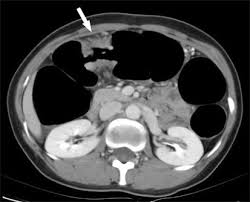

1 from Colon cancer and rectal cancer. Hi, please can anyone help me, am in so much pain. Often, mistakes in evaluating scans can lead to the incorrect determination that cancer doesn't exist in a patient. When colon cancer is detected in its early stages, there may be no symptoms present at all. One in every 20 americans (5 percent) will develop colon cancer in his or her lifetime, and about 4.4 percent of americans are affected by hemorrhoids (source: Because the symptoms of ibs, colon cancer, and some other gastrointestinal. Certain parasitic worms that can live inside the human body can also raise the risk of developing some kinds of cancer. Learn about can colon cancer be mistaken for diverticulitis) symptoms like abdominal pain, cramping, constipation, diarrhea, and rectal bleeding.

Performance Comparison Between Mri And Ct For Local Staging Of Sigmoid And Descending Colon Cancer European Journal Of Radiology from els-jbs-prod-cdn.jbs.elsevierhealth.com But when they do show up, the symptoms can mimic those of crohn's disease. Parasites that can lead to cancer. Signs and symptoms of colon cancer are often not specific, which means they may be mistaken for a number of different conditions. Colon cancer (also known as colorectal cancer) is a malignant tumor, arising from the inner wall of the large intestine. When colon cancer is detected in its early stages, there may be no symptoms present at all. A number of patients with colon cancer have been misdiagnosed with inflammatory bowel diseases (ibd) such as irritable bowel syndrome, diverticulitis, and colitis. But even if a screening is done when recommended, cancer misdiagnosis still may occur. Both conditions are common among americans.